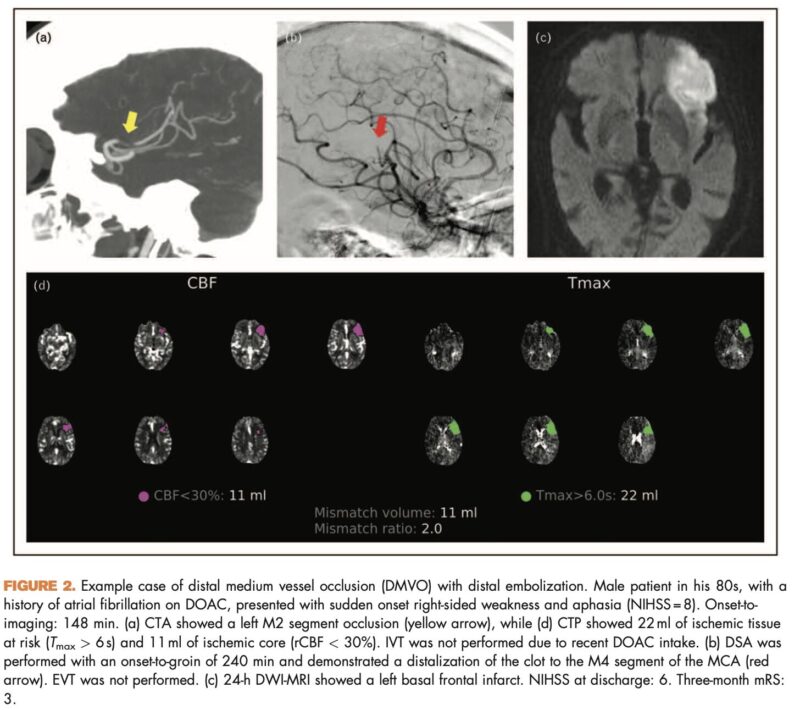

Article: Endovascular treatment of distal medium vessel occlusions

Authors: Antonio Ciacciarelli, Umberto Pensato, Johanna Maria Ospel